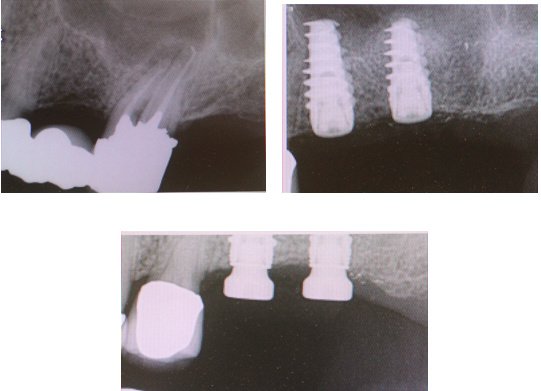

About Michael Wasemiller, DDS Creating Healthy Smiles One Patient at a Time. Dr. Wasemiller specializes in dental implants and periodontal procedures along with advanced minimally invasive sinus lift techniques. Periodontics is the field of dentistry that focuses on the area surrounding the teeth: the bone and gums. Your referring dentist focuses on the restoration of your teeth. Dr. Wasemiller works closely with your referring dentist... (Show more)